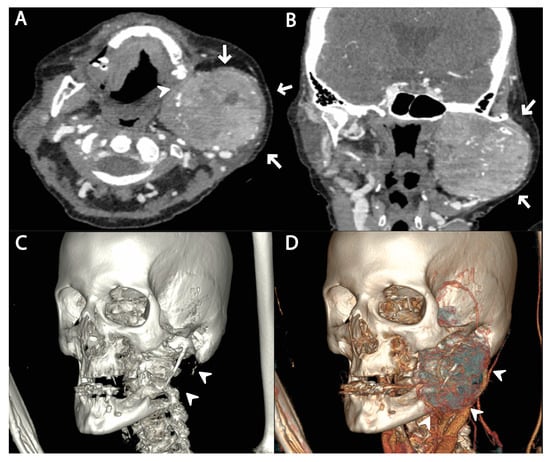

2. Case Report